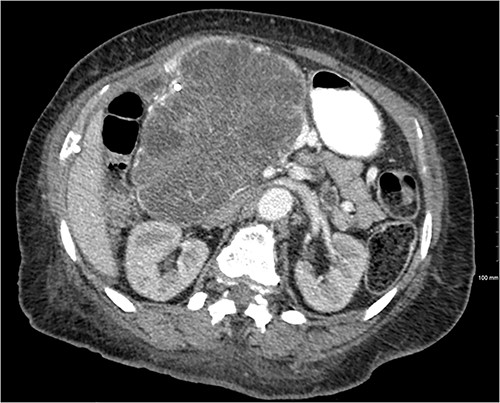

Another abdominal CT was performed redemonstrating the large heterogenous mixed attenuating mass within the right abdomen measuring 14.0 × 10.0 × 13.0 cm likely originating from the pancreatic head with resultant displacement of the PTC anteriorly and to the right with extensive pancreatic ductal dilation (Figs 2 and 3).

Coronal CT showing a large heterogeneous mass in the pancreatic head with typical honeycomb feature.

Mass effect to abdominal viscera from the 14 × 10 × 13 cm pancreatic head mass.

The mass extended up into the base of the liver, effaced the portal and superior mesenteric veins (SMV) (Fig. 4), and displaced the hepatic and superior mesenteric arteries.